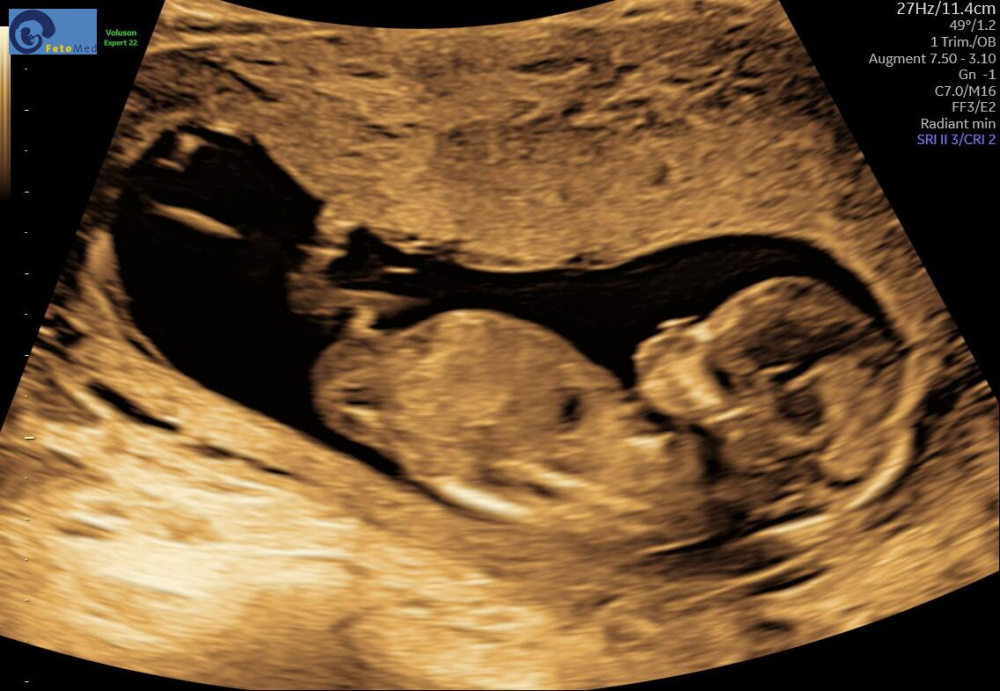

Ich hatte gestern die Nackenfaltmessung und habe neue Ultraschallbilder bekommen leider konnte man noch nicht herausfinden ob es ein Junge oder Mädchen wird. Was denkt ihr so?